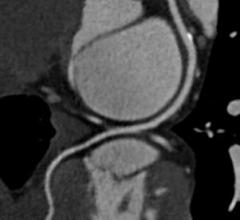

Contributing Editor Greg Freiherr offers an overview of computed tomography (CT) advances at the Radiological Society of North America (RSNA) 2015. The video includes Freiherr during his booth tours with some of the key vendors who were featuring new technology.

Computed Tomography (CT)